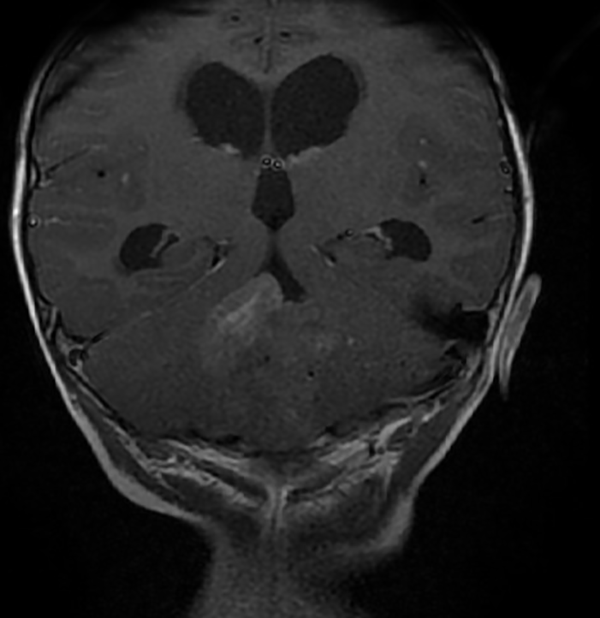

En resonancia magnética (RM) de cerebro se observa tumoración heterogénea sólida o sólido-quística con áreas de hemorragia, quistes y calcificaciones, que capta contraste en forma variable. (Fig. 1, 2, 3, 4). El patrón en espectroscopía se caracteriza por presentar pico de Colina (Cho) y descenso de N-Acetilaspartato (NAA).

Fig 3: RM corte coronal, secuencia T1 con contraste. Se observa neoformación medial, solido-quística, heterogénea de bordes irregulares en la topografía del VI ventrículo que ocupa la totalidad del mismo, que realza en forma heterogénea tras la administración del contraste. Se observa dilatación triventricular